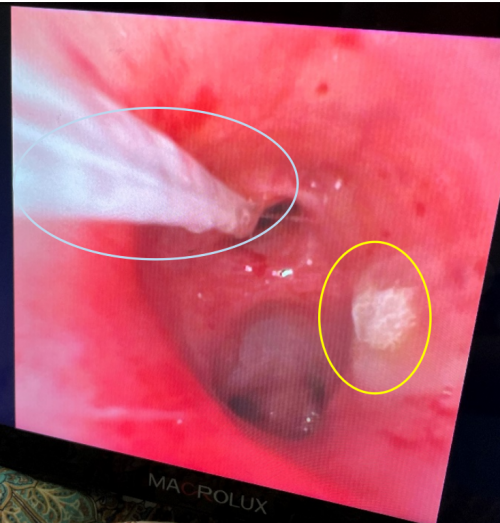

纤支镜镜下见:双下肺气管内痰液栓阻塞(白色圈),同时可见明确的菌斑(黄色圈),附着。

11.15日回报14日痰NGS结果:烟曲霉 均一化序列数63526,白色念珠菌 均一化序列数1946,甲型流感病毒H3N2 均一化序列数19844

11月15-18日病情变化:虽采取肺保护性通气策略,积极抗炎治疗,但仍发现痰液引流不畅的问题,常规排痰几乎无痰液排出,但纤支镜下见如图所示。